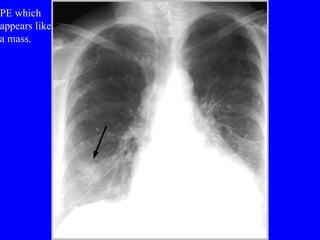

PE which  appears like a mass.